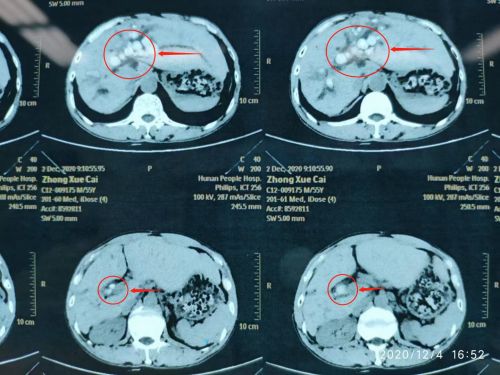

ct上可以清楚地看到胰腺肿瘤(红圈内)。

ct显示肝内外胆管均有结石。

CT检查发现,患者除肝内外胆管结石,胰腺体尾部还有一个5×3×2cm3大小的肿瘤。一边是亟待解决的全肝结石,另一边是不得不处理的胰腺肿瘤。汪新天主任医师及陈晨副主任医师多次组织开展科内讨论和术前评估,制订详尽的诊疗计划后,决定迎难而上,一次手术解决肝脏及胰腺两大疾患,使患者免受多次手术之苦。